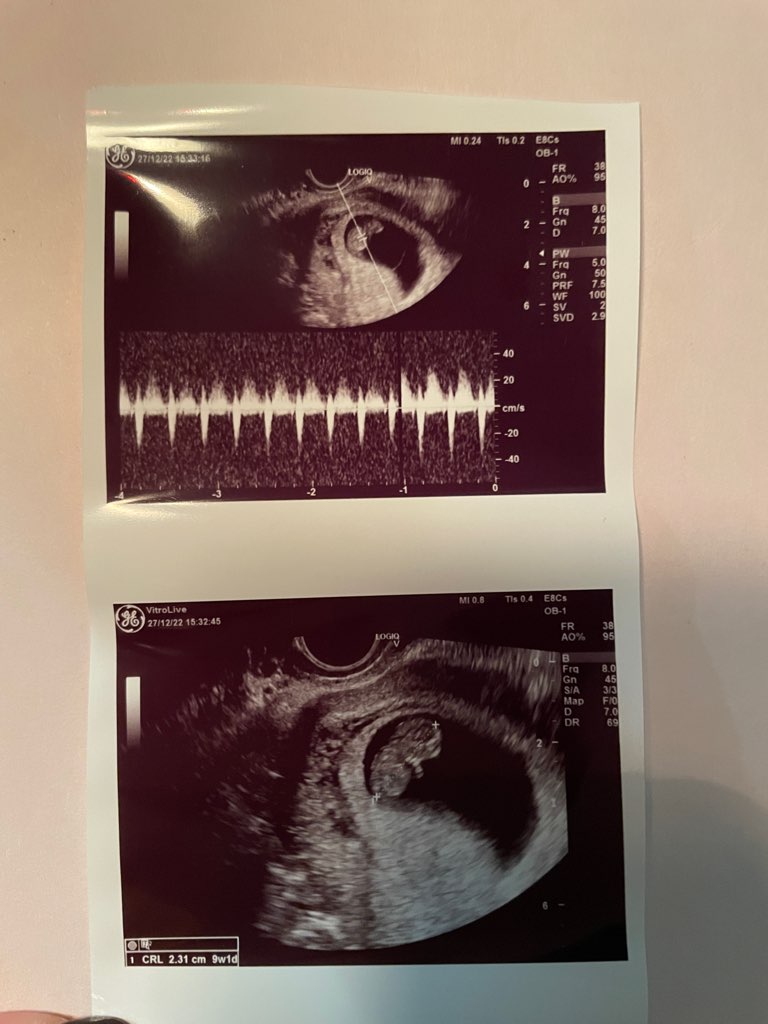

Wszystko dżiii. Wg usg ciąża nawet jeden dzień starsza. Serce biło tak szybko, że aż zapytałam lekarza, czy Dżunior jest zestresowany tak samo jak ja, ale pan doktor stwierdził, że tak serce bić powinno. Dżunior nawet zareagował na puknięcie w brzuch, więc rośnie mi kolejne dziecko, które nie przepada za ingerowaniem w jego przestrzeń osobistą

prenatalne mam wyznaczone na 23.01, bo niestety lekarz, który wykonuje to badanie, ma wcześniej urlop. Pan doktor powiedział mi, ze mam się wstrzymać z nifty do prenatalnych i tam zdecydujemy, czy w ogóle jest sens robić. Aaaa i wypytałam, czy na pewno nie mam żadnej nadżerki i pan doktor powiedział, że nieduża jest, ale czy to ona powoduje plamienia, to ciężko stwierdzić. A tu Wam wrzucam mojego 2,31cm człowieka